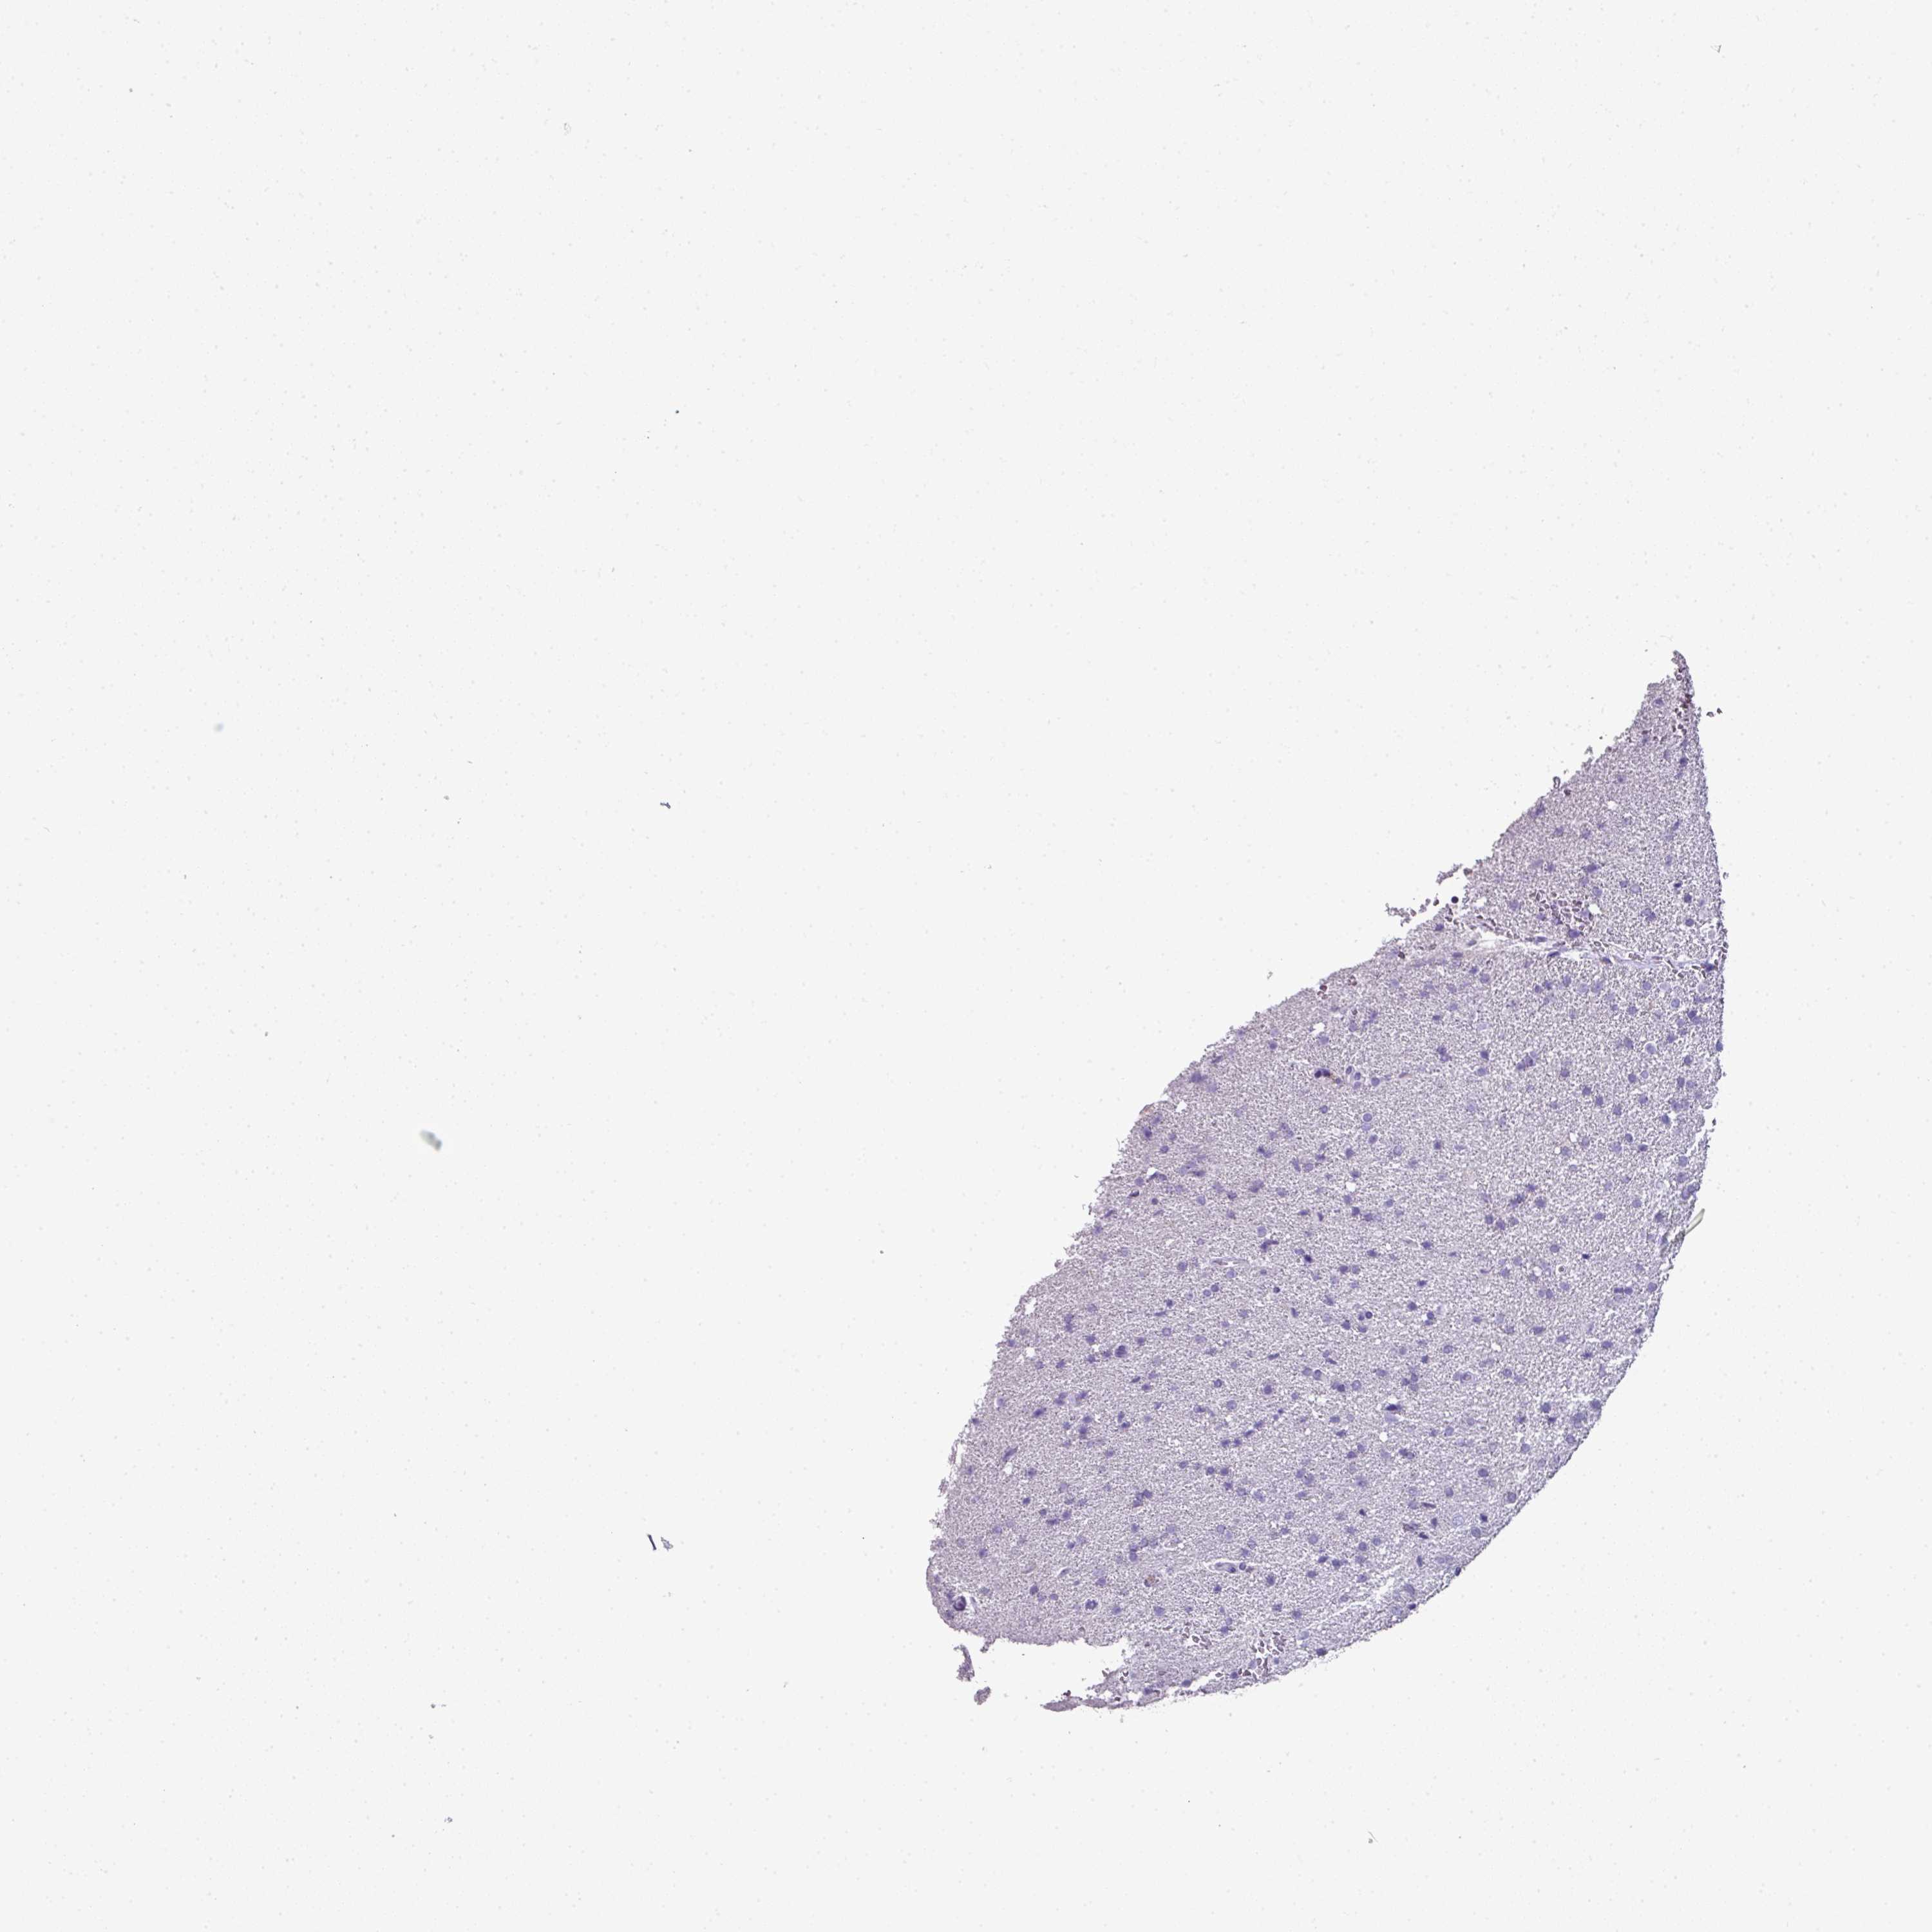

GLIOMA - Protein expressioni

A mouse-over function shows sample information and annotation data. Click on an image to view it in a full screen mode. Samples can be filtered based on level of antibody staining by selecting one or several of the following categories: high, medium, low and not detected. The assay and annotation is described here.

Antibody stainingi

Antibody staining in the annotated cell types in the current human tissue is reported as not detected, low, medium, or high, based on conventional immunohistochemistry profiling in selected tissues. This score is based on the combination of the staining intensity and fraction of stained cells.

Each image is clickable and will lead to virtual microscopy that enables deeper exploration of all samples and also displays staining intensity scores, fraction scores and subcellular localization as well as patient and tissue information for each sample.

Antibody HPA047737

Antibody CAB000110

Staining

High

Medium

Low

Not detected

Intensity

Strong

Moderate

Weak

Negative

Quantity

>75%

75%-25%

<25%

None

Location

Nuclear

Cytoplasmic/membranous

Cytoplasmic/membranous,nuclear

Glioma, malignant, High grade

Glioma, malignant, Low grade